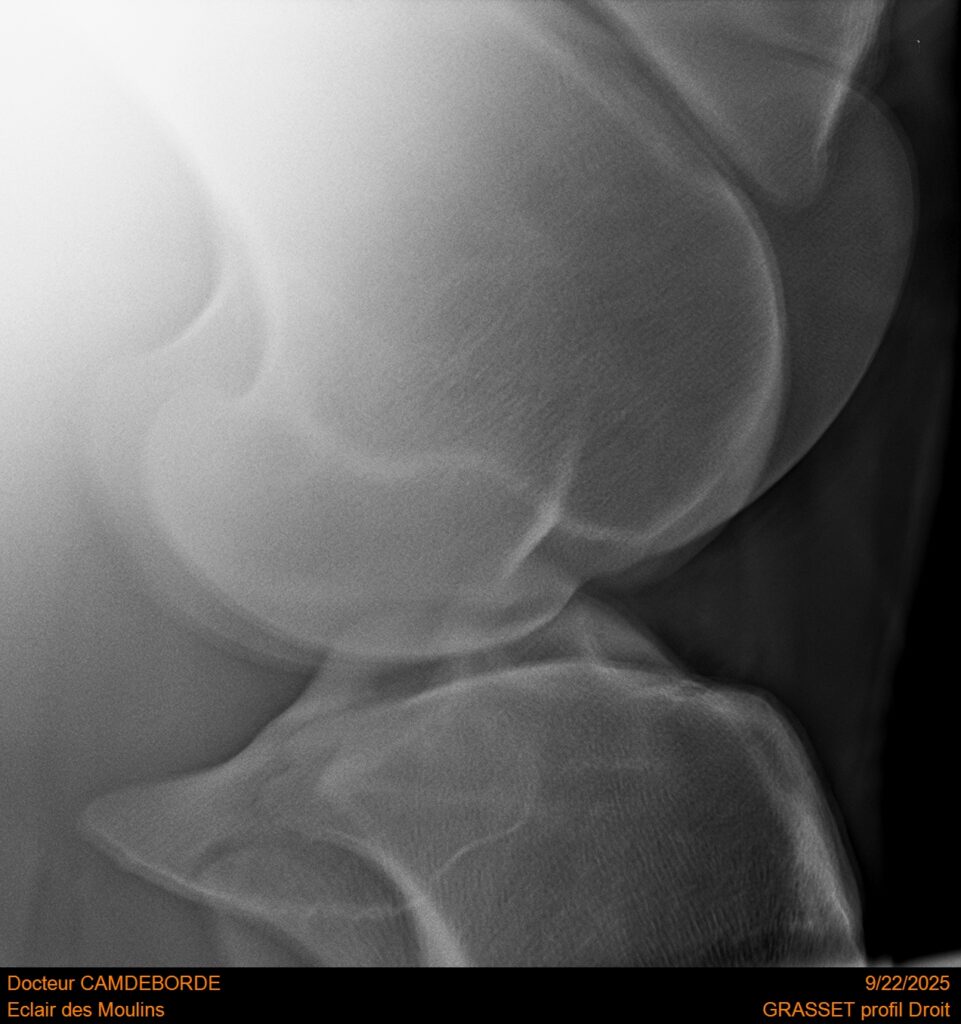

10 K ✨ TOP cheval pour épreuve Amateur ! ECLAIR DES MOULINS, selle Français de 11 ans. Classé sur 1m05. Idéal pour aller faire jusqu’à 110 voir 115, cheval pas usé (une vingtaines de parcours). Très gentil au quotidien, cheval de famille. Courageux et respectueux à l’obstacle. Bien dressé, change de pieds. Bilan pieds, boulets, jarrets, grassets et visite clinique effectuée cette semaine. il peut vivre au box comme au champs, cheval rustique. toise environ 1m60 porteur. Pour le compte de son propriétaire car manque de temps.

RADIOS ET CLINIQUE